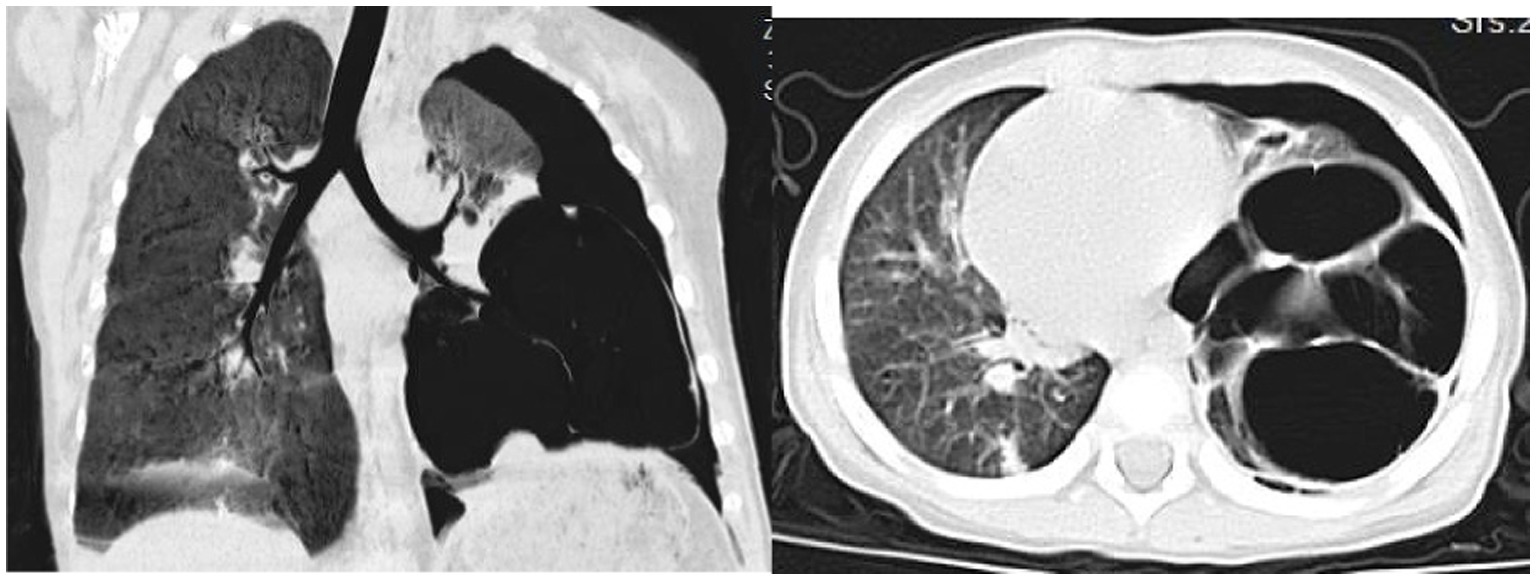

On day 32, the patient experienced worsened cough and developed respiratory distress. Chest CT (Figure 3) revealed left-sided pneumothorax with 40–50% lung compression, managed with thoracic drainage. Due to significant necrotic lung tissue and potential recurrent pneumothorax, surgical resection was advised but declined by the family. On day 41, recurrent fever prompted testing, revealing Mycoplasma pneumoniae via antigen detection on nasopharyngeal swabs using the colloidal gold method, treated with azithromycin (10 mg/kg/day intravenously for 3 days).

Figure 3

Chest CT scan on the 32th day of the illness.

Post-treatment, the patient’s temperature normalized, with occasional cough but no dyspnea or respiratory distress. The patient was discharged. Follow-up chest CT on day 67 (Figure 4) showed reduced cavitary lesion size and number, with surrounding consolidations. By 9 months post-onset, further reduction in cavity size, consolidations, fibrous strands, and localized bronchiectasis was noted. By 17 months (Figure 5), only minimal residual cavitary lesions, consolidations, and localized bronchiectasis were observed, without further significant changes compared with the 9-month follow-up. The patient’s clinical Event, Diagnostic Findings, and key interventions are summarized in Table 2.

Imaging characteristics play a pivotal role in the diagnosis and monitoring of necrotizing pneumonia. Typical radiologic findings include lung consolidation with low-attenuation areas, solitary or multiple necrotic cavities, air- or fluid-containing cavitations (either thin-walled or lacking clear walls), fibrous strands, emphysema, pneumothorax or hydropneumothorax, and pleural thickening (17). In the present case, the child initially exhibited lung consolidation, which progressed to cavitary lesions by day 15—raising clinical suspicion of necrotizing pneumonia and necessitating differentiation from congenital pulmonary malformations. On day 42, the patient developed a pneumothorax; although surgical removal of necrotic tissue was advised, it was declined by the family. By day 67, cavitary lesions had improved markedly, and further regression was seen by month 9, though bronchiectasis had emerged. By month 17, only minimal residual cavitary lesions and consolidations persisted, along with localized bronchiectasis, without further improvement.